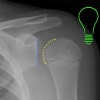

AP view에서는 팔이 내회전 상태로 인해 상완골 근위부가 백열 전구처럼 보이는 소견(light bulb sign)을 제외하면 정상 소견을 보여 오진되는 경우가 종종 있습니다.